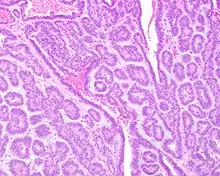

Tumors are usually small because they come to clinical attention early on in development, with an average size of about 1.6 cm.[1] There is a very characteristic appearance to the tumor when reviewed histologically.

There is a canalicular pattern with cords and ribbons showing connection points between opposing columnar cells within spaces that is called a "string of pearls" appearance.

There are often small luminal squamous balls or morules. There is a very well developed supporting tissue that is a loose, fibrillar stroma, rich in hyaluronic acid and chondroitin sulphate.[1] In a few cases small calcifications or microliths may be present. Although seldom necessary, a pathologist can do immunohistochemistry studies to confirm the diagnosis, with the cells strongly reactive with pancytokeratin, S100 protein and SOX10, with a delicate GFAP reaction around the periphery.[5][1][6][7] Even though it is a benign tumor, it must be separated from a basal cell adenoma, pleomorphic adenoma, adenoid cystic carcinoma, and polymorphous adenocarcinoma.